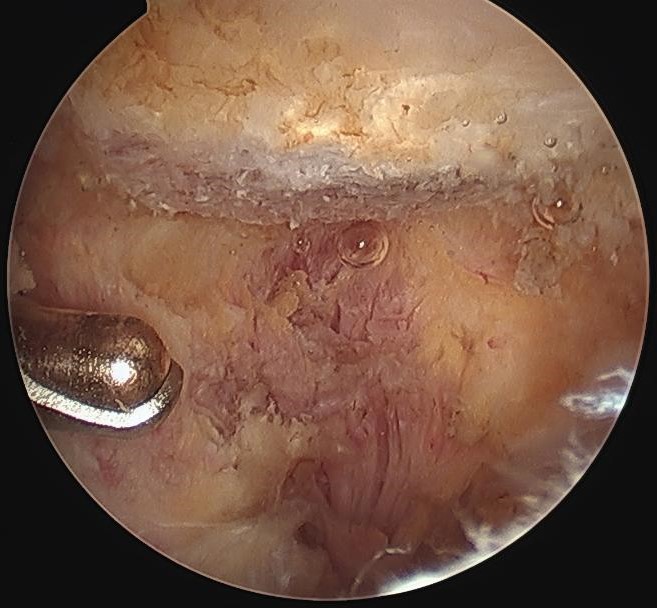

Arthroscopic acromioplasty

Technique

Beach chair / lateral

- posterior viewing portal subacromial space

- lateral working portal

- bursectomy with shaver

- electrocautery to release / resect CA ligament

- use burr to perform anterior acromioplasty

CA ligament above shaver and cuff

Large acromial spurs

Spur resection